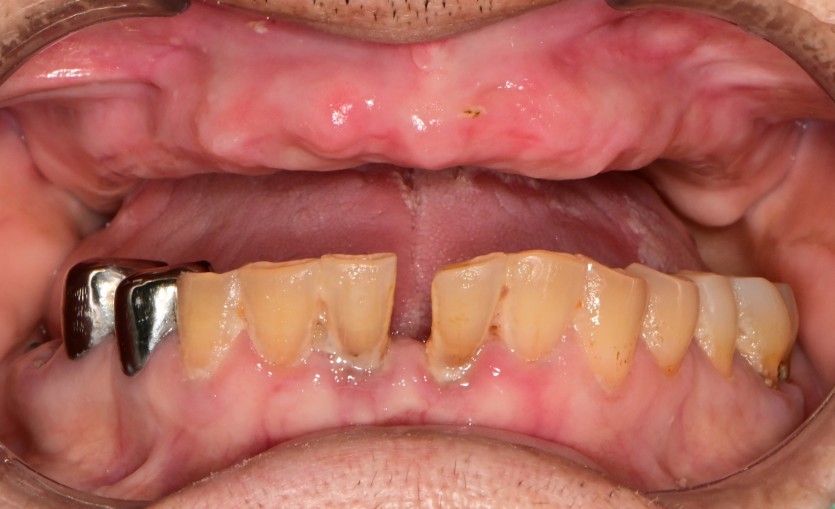

상악 풀아치 증례입니다.

8개의 임플란트로 완성하였습니다.